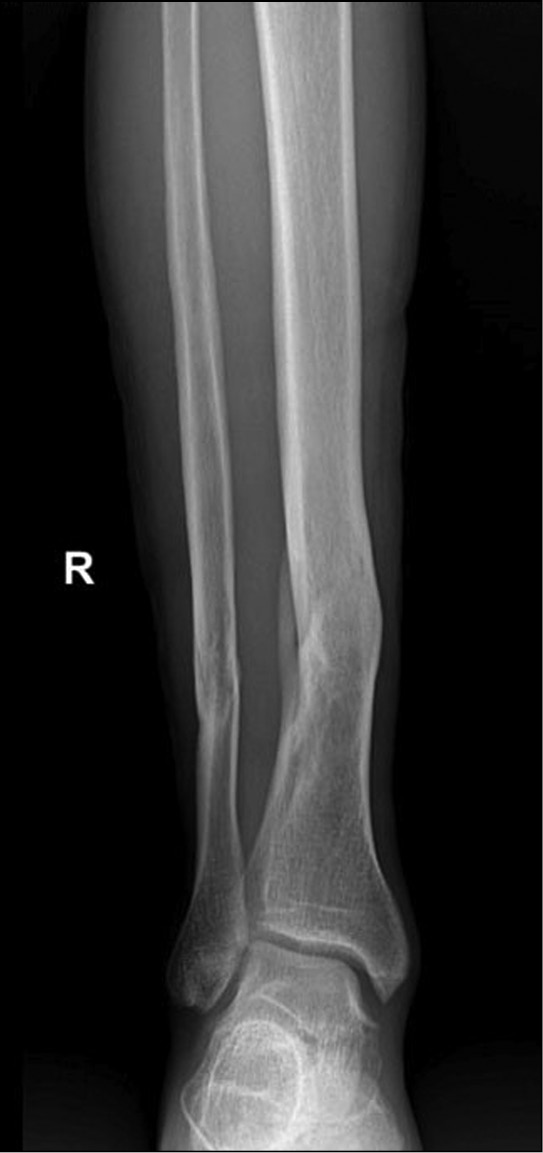

Результаты рентгенологического обследования от 20.07.2021. Судебно-медицинским экспертом изучены две цифровые рентгенограммы в электронном виде на компакт-диске на имя Р., 1987 года рождения: на рентгенограммах средней-нижней трети правой голени с захватом голеностопного сустава в прямой и боковой проекциях «свежих» костно-травматических изменений не выявлено. Определяется старый сросшийся перелом нижней трети диафиза большеберцовой кости и аналогичный старый перелом нижней трети диафиза малоберцовой кости (на одном уровне с переломом большеберцовой кости) с хорошо выраженной, плотной костной мозолью, признаками перестройки костной ткани. Линии переломов не просматриваются, имеют место выраженная посттравматическая деформация диафизов, истончение и деформация кортикального слоя в проекции сформированной костной мозоли (рис. 1, 2).

Рис. 1. Рентгенограмма правой голени в прямой проекции. Старые сросшиеся переломы нижней трети диафизов берцовых костей.

В ходе исследования судмедэкспертом рентгенограмм гр. Р. установлены и описаны несомненные признаки консолидированного перелома берцовых костей, давностью от одного года и более, с признаками хронического посттравматического остеомиелита большеберцовой кости. Изучение представленных рентгенограмм позволило эксперту прийти к выводу, что данные переломы не имеют отношения к вышеописанным событиям от 20.07.2021, поэтому судебно-медицинской оценке не подлежат.